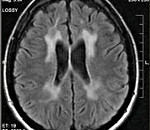

Диагностические мероприятия имеют комплексный характер и позволяют отдифференцировать метахроматическую лейкодистрофию от других нейродегенеративных заболеваний и других форм лейкодистрофии. Проводится люмбальная пункция, при исследовании цереброспинальной жидкости определяется повышенная концентрация белка, дефицит арилсульфатазы, белково-клеточная диссоциация. Электромиография выявляет увеличение длительности проведения нервных импульсов. КТ головного мозга визуализирует расширенные желудочки и определяет пониженную плотность белого церебрального вещества. МРТ головного мозга выявляет очаги демиелинизации.